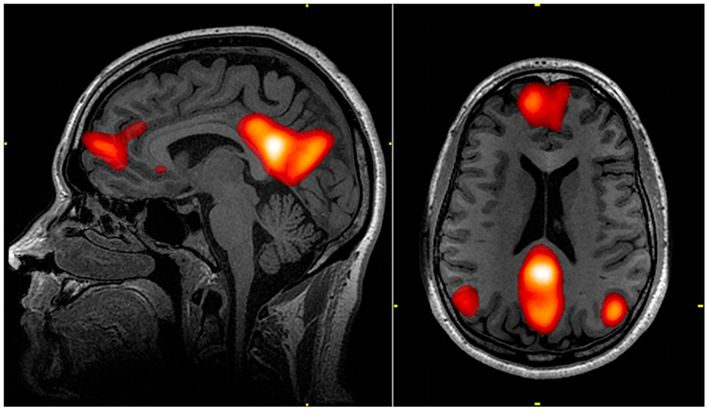

The brains default mode network (highlighted in red)